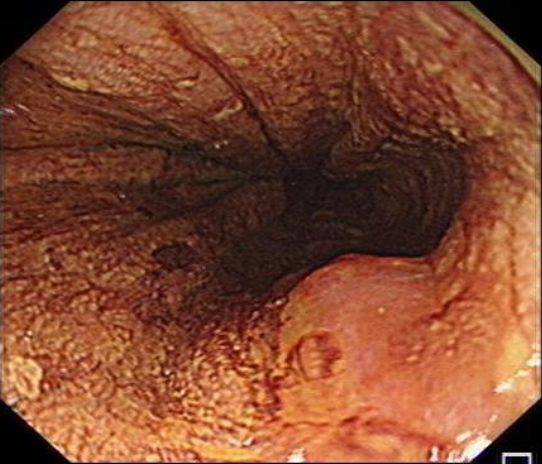

在众多的中药中,有一些被广泛应用于抗癌治疗。例如,补益类的黄芪,能够补气升阳,增强免疫力,对于术后体虚的患者具有显著的疗效。灵芝则能够调节免疫,改善放化疗后的抑制状态。在清热解毒方面,半枝莲抑制癌细胞增殖,多用于消化系统肿瘤的治疗。白花蛇舌草则能够诱导肿瘤细胞凋亡,常与半枝莲配合使用。活血化瘀类的莪术能够消散肿块,改善肿瘤微环境,而三七则具有止血散瘀的功效,能够缓解癌性疼痛。

当我们谈论中药抗癌时,需要保持理性和警惕。要避免被一些视频或宣传所误导,声称某几味中药是“癌细胞天敌”或“能根治癌症”,这些宣传往往缺乏实际的可信度。要明确中药在癌症治疗中的地位,它并不能替代正规的治疗方式。对于恶性程度高的癌症,如肝癌、胆管癌等,单纯中药治疗可能无法取得理想的效果,延误最佳治疗时机。